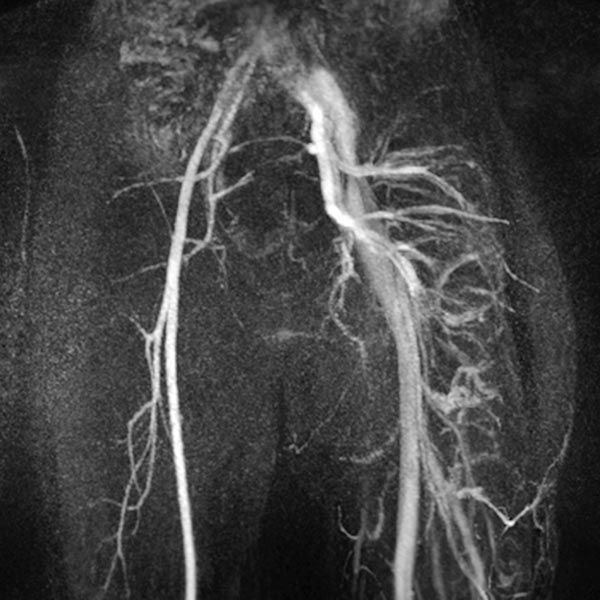

MIP reconstruction of a contrast-enhanced dynamic MR angiography of the pelvis and thighs. While an arterial phase is still present on the normal right side, the arteries and veins of the left side are massively dilated and already contrasting the draining veins because of the multiple arteriovenous fistulas seen in Parkes-Weber syndrome.